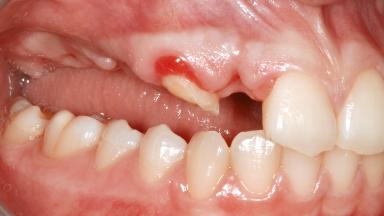

A 47-year-old woman who had suffered from aggressive periodontitis requiring a number of periodontal interventions over more than 10 years was referred by her general dental practitioner and periodontologist for bone augmentation and implant therapy. Her failing dentition had already been scheduled for extraction. The patient expressed a desire for implant-supported fixed restorations and esthetic improvement of her lower face. She had agreed to consult with a maxillofacial surgeon after the referring dentist had suggested bone augmentation. An initial examination by the maxillofacial surgeon revealed mobility of all residual teeth in a patient who was very unhappy with the function of her removable partial dentures. Due to periodontally migrated flaring teeth and loss of occlusal support, the vertical dimension of occlusion was dramatically reduced. The patient was displeased with her lower face because of deepened nasolabial, commissural, and supramental folds.